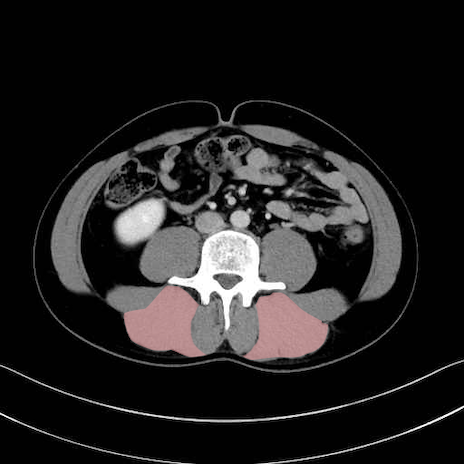

脊柱起立筋 (Erector spinae)

多裂筋 (Multifidus)

2. 腸腰筋群と骨盤底筋

大腰筋 (Psoas major)

腸骨筋 (Iliacus)

肛門挙筋 (Levator ani)

3. 殿部の筋肉(表層・中層・深層)

大殿筋 (Gluteus maximus)